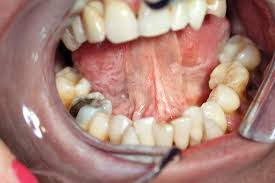

Oral Cancer Dr Kanishk Mehta Udaipur from productimages.withfloats.com Floor of the mouth cancer is cancer that begins on the tissue underneath your tongue. Tongue cancer is a type of mouth cancer, or oral cancer, that usually develops in the squamous cells on the surface of the tongue. Mixed red and white patches and bright red patches are also signs of trouble. It may be numb or firm to feel and doesn't fade away over time. Tongue cancer is highly curable if caught in the early stages 2. The hardest part of recovery: A red patch under the tongue. Smokers are five times more likely than nonsmokers to develop oral tongue cancer.

Floor of the mouth cancer most often begins in the thin, flat cells that line the inside of your mouth (squamous cells).

Do to the location of my tongue cancer which is at the base of the tongue (can not be seen without bent mirrors or a remit) radiation is no other course of action. They may look like a patch or a lump or look like an ulcer. Floor of the mouth cancer is cancer that begins on the tissue underneath your tongue. When possible, use one finger inside your mouth and one finger on the outside, corresponding to the same place and feel for unusual bumps, swelling or tenderness. Seeing a red or white patch on you gums, lining of mouth, tonsil or tongue is a sign of squamous cell carcinoma.

A white or red patch inside your mouth or on your lips may be a potential sign of squamous cell carcinoma. Some symptoms of mouth cancer are noticeable, that makes it possible to detect mouth cancer in its early stages. Women and people of 45 years of age and above are more vulnerable to. Oral cancer can pose a serious health risk.consequently, many patients become concerned when they develop unusual spots or sores in the mouth. Removable devices that look like dental retainers can fill in for lost tissue or. Individuals who smoke or consume large amounts of alcohol are at an increased risk and need to be screened regularly. Mouth cancer of the lips and tongue have a better prognosis. These patches are made up of cells that can lead to cancer. It can begin in the lips, tongue, gums,. It's important to be aware of the symptoms of mouth cancer so you can contact your gp or dentist if you notice anything abnormal. Floor of the mouth cancer most often begins in the thin, flat cells that line the inside of your mouth (squamous cells). Tongue cancer is a type of mouth cancer, or oral cancer, that usually develops in the squamous cells on the surface of the tongue. They may look like a patch or a lump or look like an ulcer.